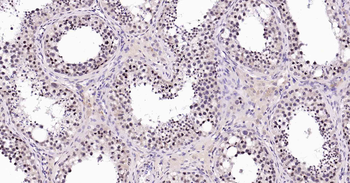

100 μl, 50 μl, 25 μl - Rad51 Recombinant Rabbit Monoclonal Antibody [orb608069]Featured

IF, IHC-Fr, IHC-P, WB

Human, Mouse, Rat

Mouse, Rat

Rabbit

Recombinant

Unconjugated